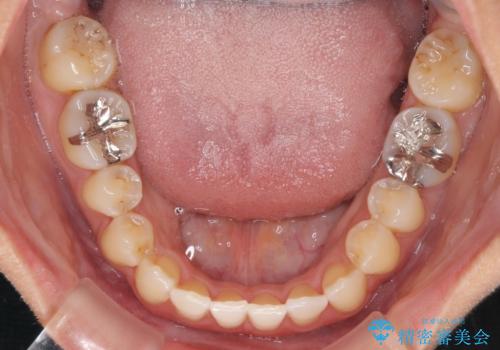

前歯のデコボコ インビザラインによる矯正治療

- 上下前歯の叢生と奥歯の反対咬合を気にして来院された患者様です。

インビザラインを用い、下顎はIPR(歯と歯の間を削る)と歯列全体を後方に移動させ、上顎は側方に拡大させることで歯列を改善していくこととしました。

骨格的に下顎が左側前方にずれているため、上下正中のズレや左右奥歯の咬み合わせを理想的な状態とすることは困難でした。